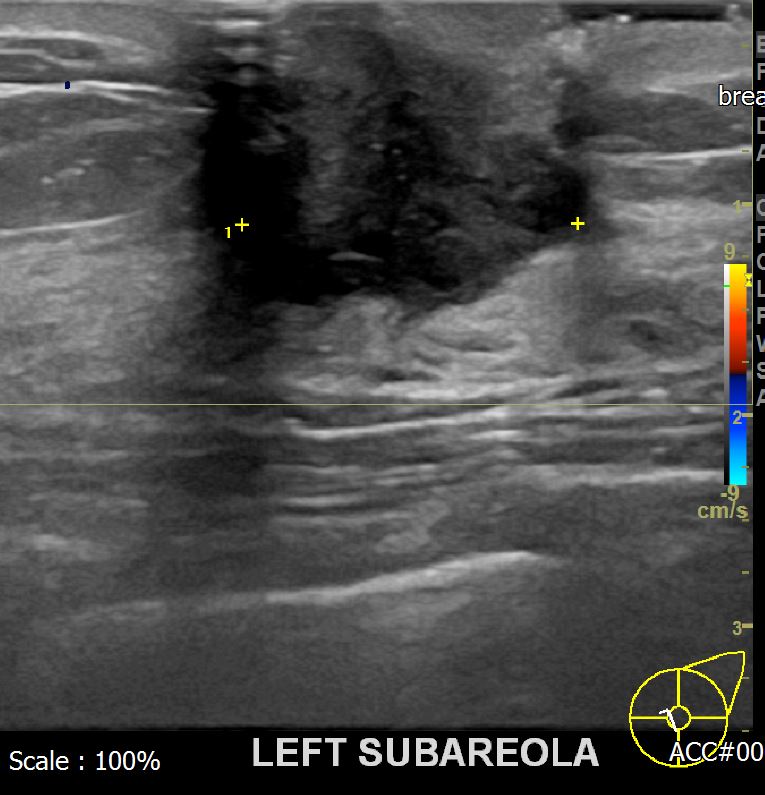

상기환자 유방의 염증증상있어 내원하신 40대 여성분으로 초음파검사후

좌측유방의 의심스러운 혹 조직검사시행후 유방암 진단되었읍니다